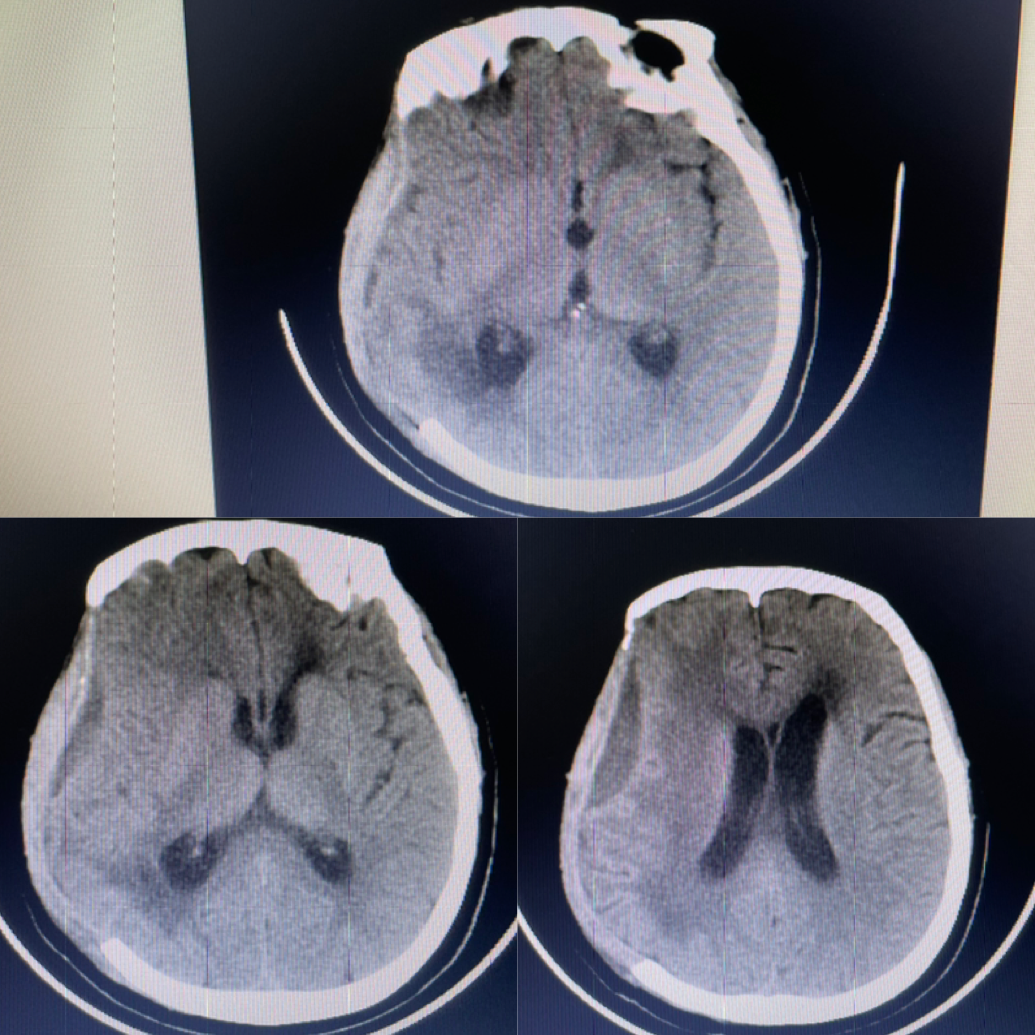

入院ct提示:右侧颞叶大量脑出血

颞叶血肿破溃形成硬脑膜下血肿

进一步增加脑出血颅内占位效应 颅内高压

术后一月复查